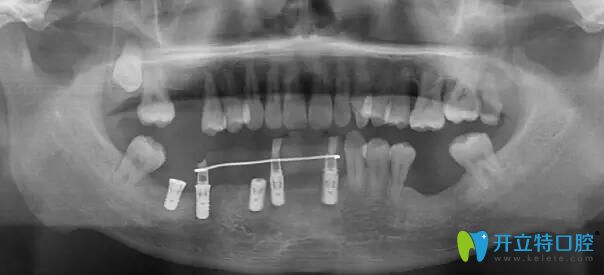

南通摩爾口腔術(shù)前ct

術(shù)前全景片,下頜大部分牙齒缺失,殘留牙牙槽骨吸收明顯,從醫(yī)生的角度看,一個三十歲左右的青年人,牙病如此嚴重,實屬罕見。經(jīng)過了解,王先生從小害怕看牙,有牙齒問題遲遲未做治療,拖延病情至今。本次尋找周院長看牙,一是自己牙齒情況已經(jīng)嚴重影響到自己的正常生活,二是經(jīng)過多方打聽,相信周院長的技術(shù)一定可以幫助自己擺脫長期缺失牙的狀況。

南通摩爾口腔術(shù)前手術(shù)設計

周文清院長根據(jù)王先生的CT判斷,保留33號、34號、35號牙,術(shù)中拔除44號、42號、41號、31號牙。采用數(shù)字化3D導板導航于32號、42號、43號、45號、46號牙位即刻植入5顆ITI種植體。